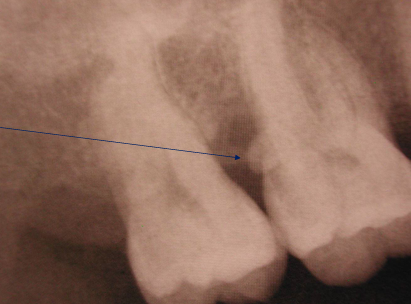

-mobility

-widened PDL

-widening of the PDL

-could happen if restoration is too high on occlusal